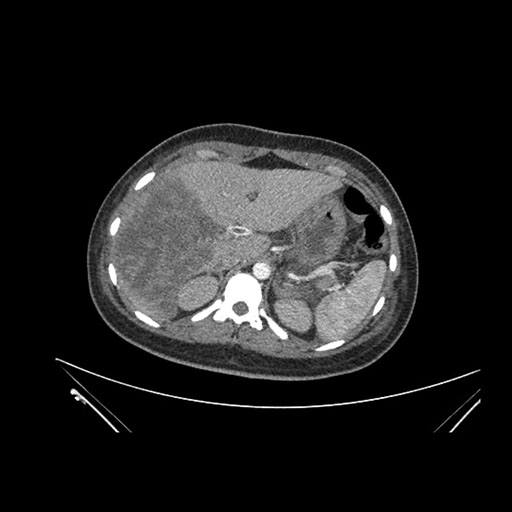

Imaging Analysis

Look through the patient's CT scan to identify any areas of concern for the necessary procedure.

Axial Venous

Based on initial findings, which issue(s) would you be most concerned about?